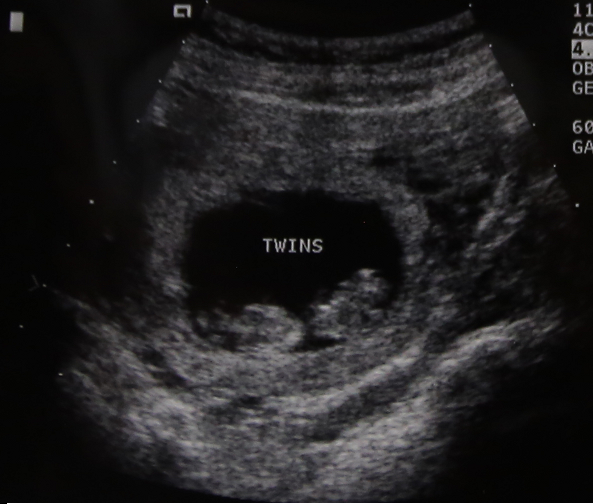

Here are the babies first picture!